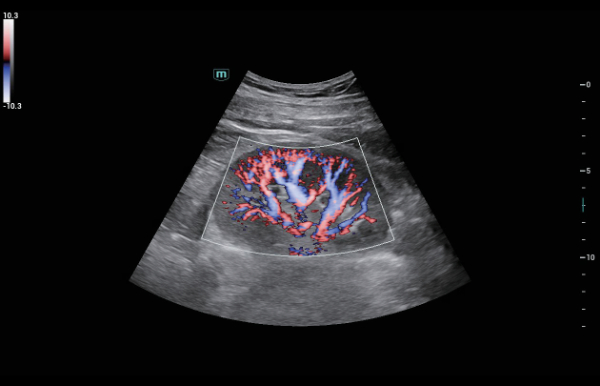

Indipendentemente dalle attività svolte in ospedale o in clinica, oppure se si desidera affinare le proprie capacità nella diagnostica per immagini generale negli ambiti della salute della donna o cardiovascolare, questa serie di soluzioni fornirà potenti strumenti per essere sempre un passo avanti.

Soluzioni di diagnostica per immagini complete con tecnologia ZST+

La piattaforma ZST+ è un'innovazione straordinaria, che rappresenta un'evoluzione nel campo dell'ecografia. Grazie alla trasformazione delle metriche a ultrasuoni dal beamforming convenzionale all'elaborazione basata sui dati di canale, supera la tradizionale limitazione del trade-off tra risoluzione spaziale, risoluzione temporale e uniformità dei tessuti, offrendo una qualità d'immagine eccezionale per infinite soluzioni di imaging con miglioramenti continui.